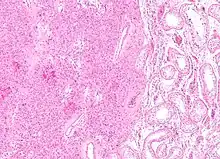

| Micrograph of a granulosa cell tumour, a type of sex-cord–gonadal stromal tumour. H&E stain. | |

Low magnification micrograph of a granulosa cell tumour. H&E stain.